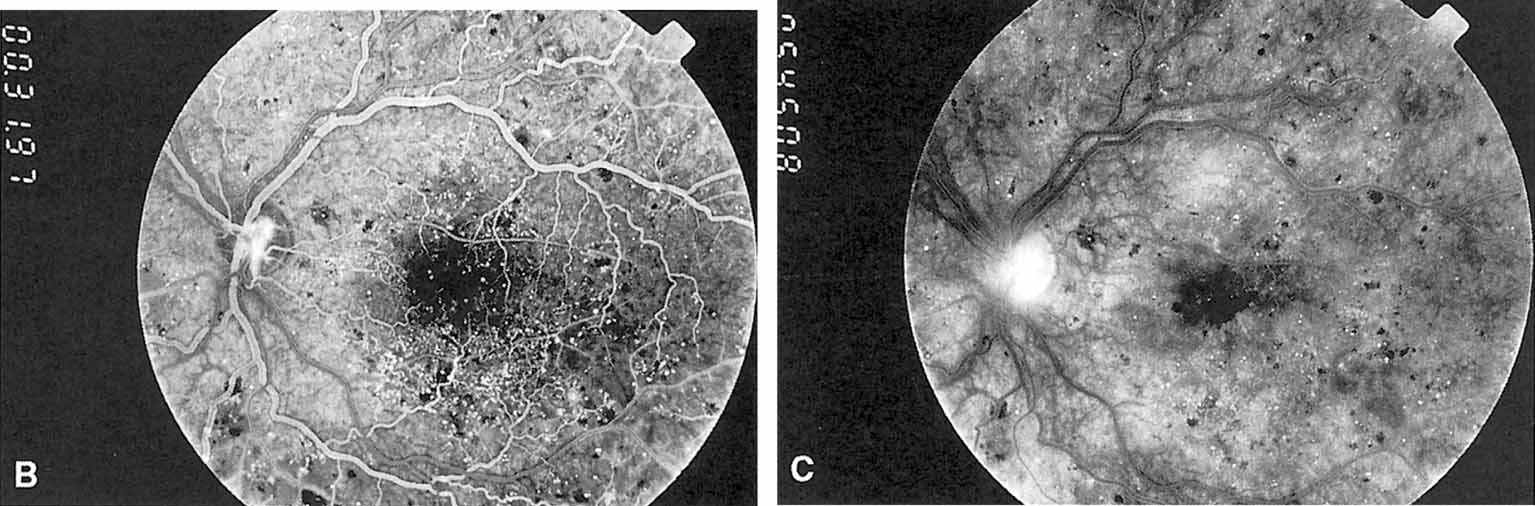

Fig. 3 A. Diabetic retinopathy with multiple microaneurysms, dot hemorrhages, and early neovascularization of the optic disc (NVD). A small blot hemorrhage is seen inferiorly. B. Continued. Midphase of the fluorescein angiogram. Patent microaneurysms are seen as hyperfluorescent dots. Note that most microaneurysms cannot be seen ophthalmoscopically. There is some enlargement of the foveal avascular zone because of some occluded capillaries. Temporally there is a larger zone of capillary nonperfusion. The NVD is beginning to leak. C. Late phase of the fluorescein angiogram showing diffuse leakage of fluorescein into the macula.

It is often difficult to distinguish a small dot hemorrhage from a microaneurysm by ophthalmoscopy alone. On fluorescein angiography patent microaneurysms will fill with dye quickly and then leak,5 unlike a small dot hemorrhage that will block fluorescence (see Fig. 3). However, angiography cannot distinguish a hemorrhage from a microaneurysm filled with clotted blood. Because fluorescein passes easily though them, we usually see many more microaneurysms on fluorescein angiography than are apparent on examination.6

When the wall of a capillary or microaneurysm is thin, it may rupture, giving rise to an intraretinal hemorrhage. If the hemorrhage is deep (i.e., in the inner nuclear layer or outer plexiform layer), it usually has a round or oval shape (“dot or blot”) (see Fig. 3). Superficial (nerve fiber layer) hemorrhages, on the other hand, become flame- or splinter-shaped indistinguishable from that seen in hypertensive retinopathy. Although people with diabetes with normal blood pressure may have multiple splinter hemorrhages, they should nevertheless have their blood pressure checked because a frequent complication of diabetes is systemic hypertension.